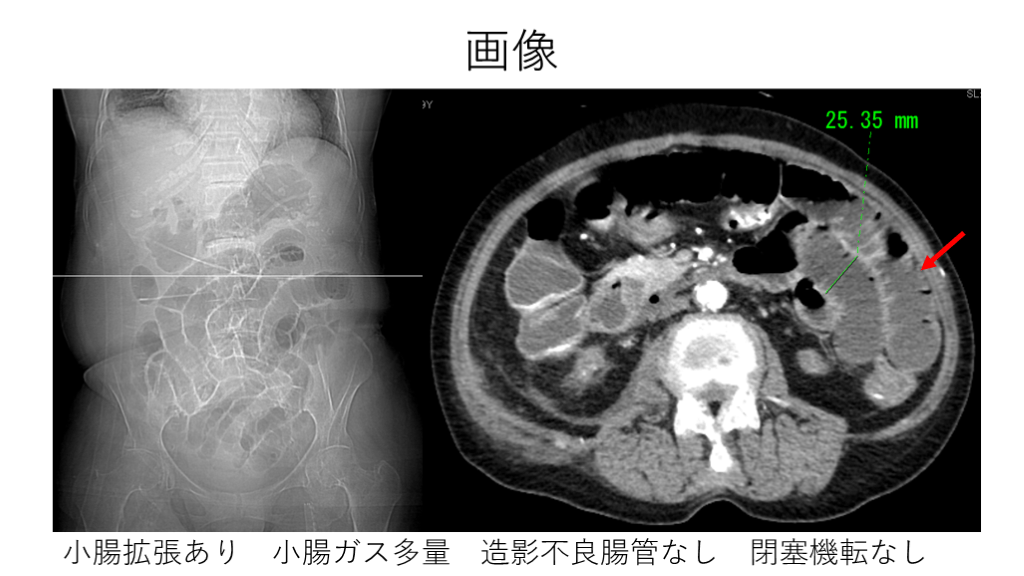

画像 小腸拡張あり 小腸ガス多量 造影不良腸管なし 閉塞機転なし

画像 麻痺性イレウスの診断で内科で入院加療。